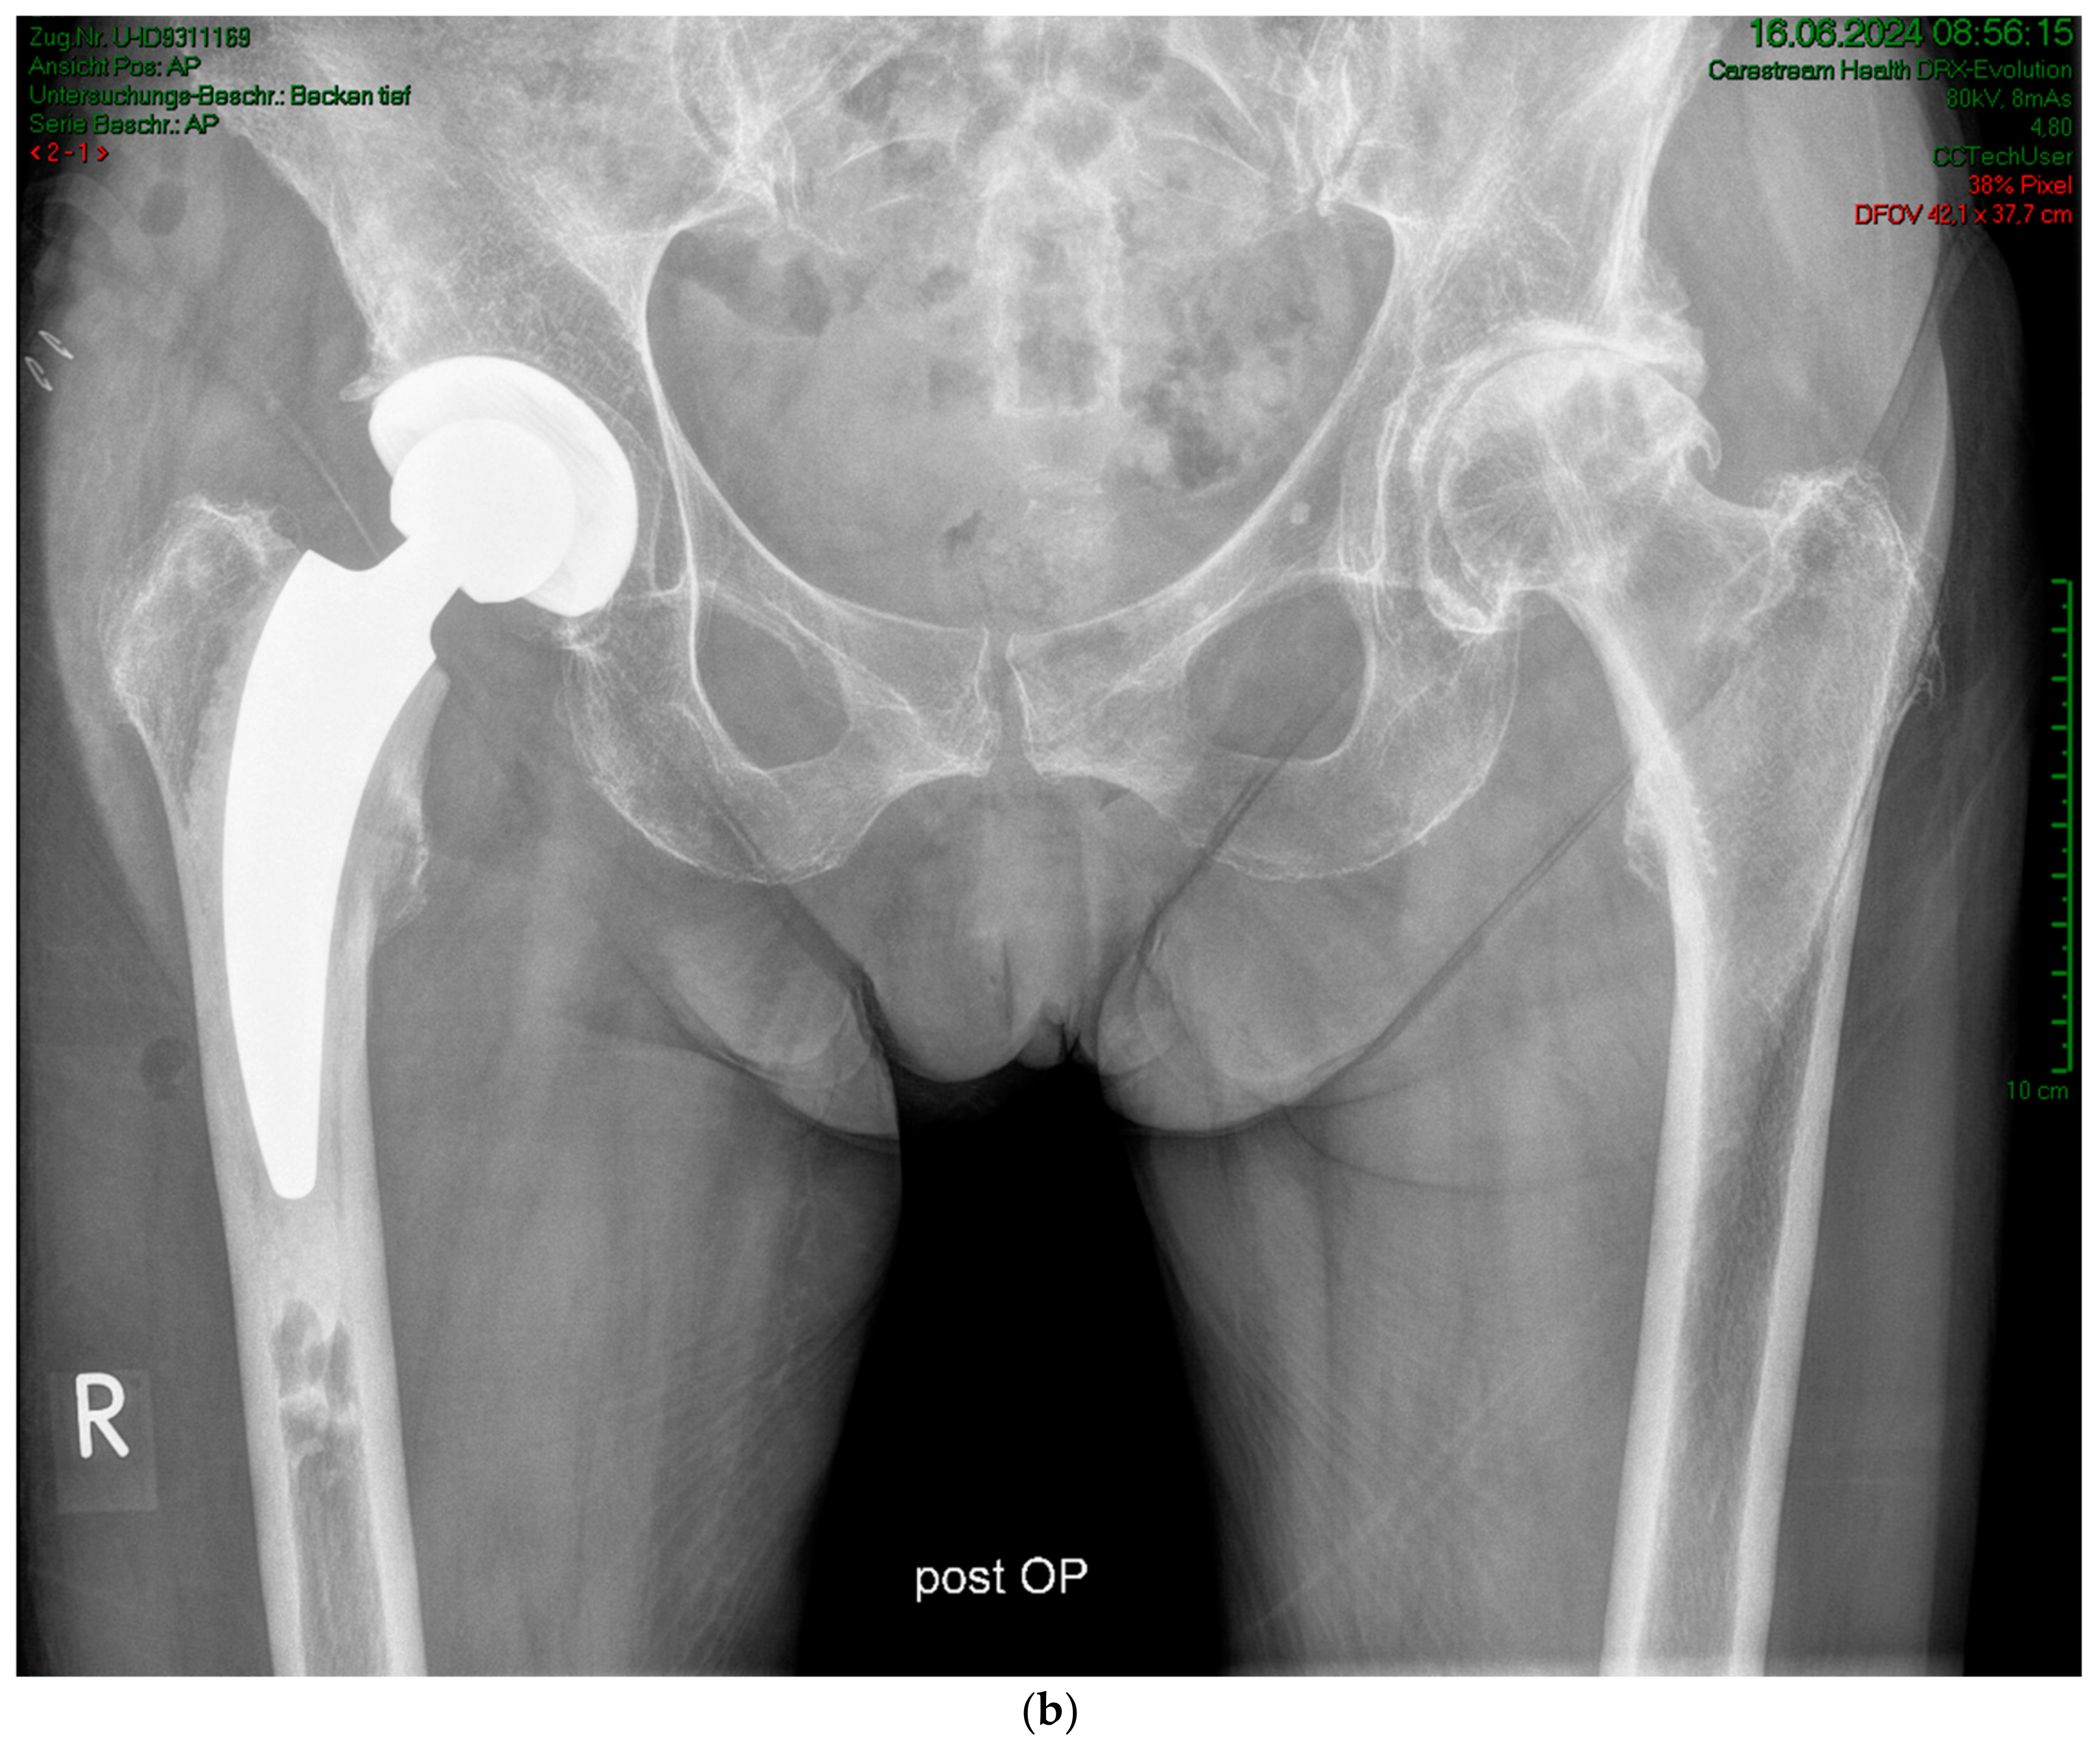

2. Materials and Methods